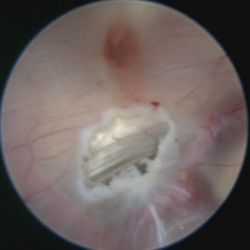

Das hierfür verwendete Verfahren ist die endoskopische Ventrikulozisternostomie (englisch endoscopic third ventriculostomy = ETV). Hierbei wird ein feines Endoskop in die erweiterten Hirnkammern vorgeschoben und damit am Boden des 3. Ventrikels in einem Areal, welches keine Funktion enthält, unter Sicht meist mit einem Speziallaser eine Öffnung geschaffen.